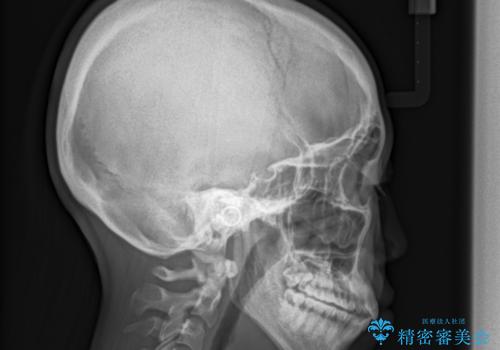

- 上顎の骨格性拡大+両側第1小臼歯抜歯 によりスペースを獲得、フルリンガルによるワイヤー矯正を計画した。

骨格的要因を背景にもつ不正咬合のため、歯列矯正単独での改善は困難と判断しましたが、患者さんとの相談の結果、歯列矯正単独で可能なところまで一緒に頑張りましょうということで、治療をすすめました。

シビアな叢生や開咬も改善することができ、想像以上の改善に時間をかけた甲斐があったと満足していただけました。